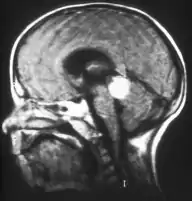

Traditional ultrasound B scan can detect calcifications in the tumour while high-frequency ultrasound B scan is able to provide higher resolution than the traditional ultrasound and determine the proximity of the tumour with front portion of the eye. MRI scan can detect high-risk features such as optic nerve invasion; choroidal invasion, scleral invasion, and intracranial invasion. CT scan is generally avoided because radiation can stimulate the formation of more eye tumours in those with RB1 genetic mutation.[24]

Aspect of trilateral retinoblastoma on MRI